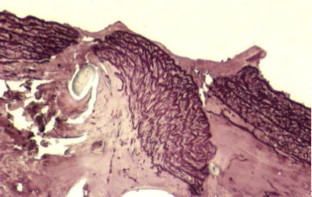

Former animal studies on laser-assisted microvascular anastomosis performed with CO2-, argon-, diode-, Holmium:YAG- and Nd:YAG-lasers had already proven the stability of the anastomotic sites. Tissue damage remained minimal along the anastomosis, while duration of the surgeries decreased significantly compared to that of traditionally implemented microvascular sutures. In addition to this, foreign body reaction next to end-to-end anastomosis appeared to be minimal due to fewer traditional stitches. This animal study was designed in order to investigate the durability and the histological properties of microvascular anastomosis assisted by KTP-532 laser. Twenty-one Wistar albino rats were used: in nine animals the KTP-laser-assisted microvascular anastomosis was carried out on the femoral artery. Those nine animals were divided into three groups and each of them consisted of three rats. The animals in these three groups were sacrificed 4 h, 1 and 4 weeks following the surgery, respectively. In three additional animals laser-assisted microvascular anastomosis was done on the abdominal aorta. Conventional microvascular sutures were carried out on femoral arteries of further nine animals in the control group. The healing process of the femoral arteries is documented with figures of histological slides both in the laser-treated and in the conventionally operated group of rats. The KTP-laser-assisted microvascular anastomosis failed on the abdominal aorta, as strong bleedings occurred after the traditional sutures had been taken out. However, the coagulative effect of the KTP-laser could still be used. The authors share the opinion that the success of the laser-assisted end-to-end microvascular anastomosis does not depend on the wavelength of the applied laser, but can be affected by both the calibre of the vessel and the intraluminal pressure.

Fig. 1

Fig. 2

Fig. 3

Fig. 4

Fig. 5

Fig. 6

Fig. 7

Fig. 8

Fig. 9